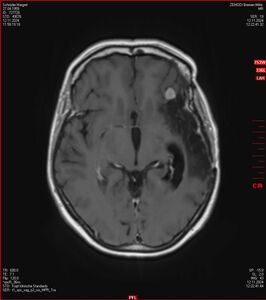

MRT vom 12. November 2024

So nun ein paar neue Bilder aus meinem Kopf. (Durch klicken bekommt man eine größe Ansicht eines Einzelbildes).

Die letzten drei Bilder Zeigen aus meiner Sicht den Tumor, der im Jahr 2021 bestrahlt wurde.

Ich denke, in den letzen 12 Monaten sind da ein paar Rezidive gewachsen,  vor 12 Monaten waren sie auch schon zu erkennen - vorher noch nicht. Nun hoffe ich auf den Rat des Spezialisten. Hoffendlich kann man etwas machen.